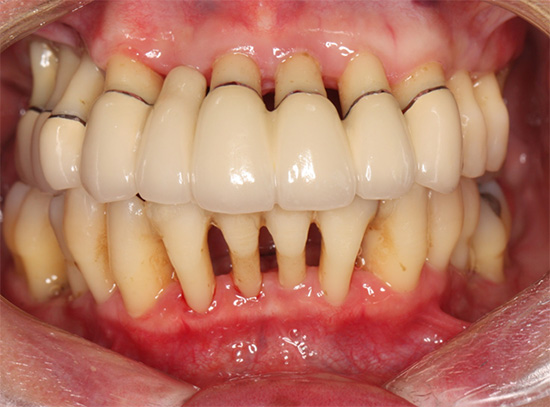

重症な歯周病患者さんの口腔内写真

40代女性

初診時、歯の動揺な出血を訴えて来院。

口の中全ての歯が重症の歯周病を発症

治療終了後7年経過した口腔内写真

治療終了時

歯周病による感染や炎症をブラッシングと歯周病治療を行い、動揺する歯を固定して機能の回復を行った。この治療は、患者さんのブラッシングが十分でないと、逆に進行してしまい、また精度の高いブリッジを作らないと、早期に再治療や最悪、抜歯になってしまう可能性がある。

幸い、この患者さんは非常に治療に協力していただき、また3ヶ月ごとに来院してチェックとクリーニングをお手伝いしている。

治療費の合計 およそ90万円

治療期間 およそ10ヶ月